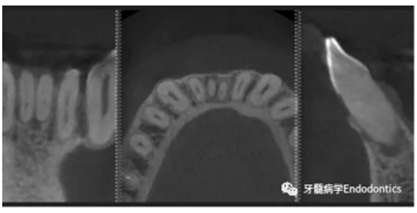

31、41叩痛明顯,牙冠變色(圖1)。溫度和牙髓電活力測試無反應。兩張從不同角度拍攝的x線片顯示,相對于側切牙,雙側下中切牙都有嚴重的根管鈣化(圖2)。41有明顯根尖周暗影,31根尖周暗影不明顯。為進一步證實31是否存在根尖周病變,同時精細觀察31、41的復雜結構,根據歐洲牙髓病學會CBCT應用指南(2014),對患牙拍攝小視野、高分辨率CBCT。CBCT影像證實31、41均伴有根尖周炎和嚴重的根管鈣化(圖3)。距離根尖4mm可見根管影像。 由于患牙根管解剖結構較為復雜,筆者決定使用特殊設計的微型鉆頭(直徑0.85mm)進行“數字化導航牙髓治療”。 因此對下頜進行口內掃描(圖4)。用coDiagnostixTM軟件(Dental Wings Inc.,Montreal,Canada)將CBCT和口內掃描的數據進行處理,該軟件主要用于引導種植。通過該軟件對兩個掃描圖像進行疊加后,虛擬鉆頭尖端沿牙長軸對準根管下段可見部分(圖5)。三維檢查虛擬鉆的正確位置。

圖3.下頜前牙CBCT影像。

圖4.下頜牙口內表面掃描的表面鑲嵌語言(stl-)數據。